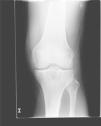

En la analítica se objetivó una uricemia de 9,4mg/dl y GGT 166 U/dl. El resto de los parámetros (hemograma, TSH, CPK, Factor reumatoide, HLA B27, anticuerpos antipéptido cíclico citrulinado, inmunoglobulinas, orina y uricosuria de 24h) fueron normales. Se realizó radiografía de pie izquierdo (fig. 1) que mostró erosiones marginales de bordes bien delimitados en la cabeza del primer metatarsiano, con aumento de partes blandas adyacente. La radiografía de rodilla izquierda (fig. 2) presentaba lesiones líticas de bordes bien delimitados en epífisis tibial y cambios degenerativos incipientes a nivel femorotibial. Se realizó artrocentesis de la rodilla izquierda. Con visualización de cristales de urato monosódico en el líquido sinovial (LS). El cultivo del LS fue negativo.